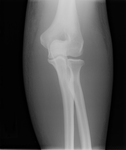

Anteroposterior x-ray view of a reduced elbow dislocation

Personal collection of Dr Paul Novakovich